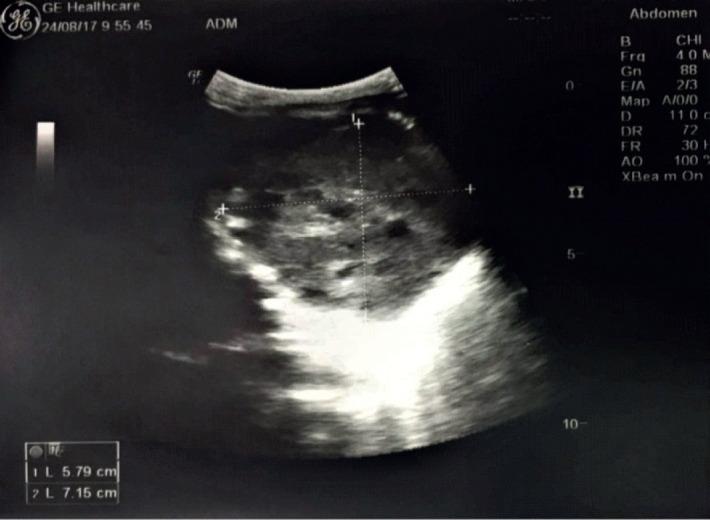

The aim was to present a case of a 4 month-old infant with type II PPB, who had a negative result for DICER1 mutation in next generation sequencing. To detail the clinical presentation of this patient, we present radiographic and ultrasound findings and results of histopathological analysis, as well as genetic and scintigraphic findings and chemotherapy treatment.

目的是介绍一例 4 个月大的婴儿患有 II 型 PPB,下一代测序结果为 DICER1 突变阴性。为详细介绍该患者的临床表现,我们展示了放射学和超声检查结果以及组织病理学分析结果,以及遗传和闪烁扫描结果和化疗治疗。